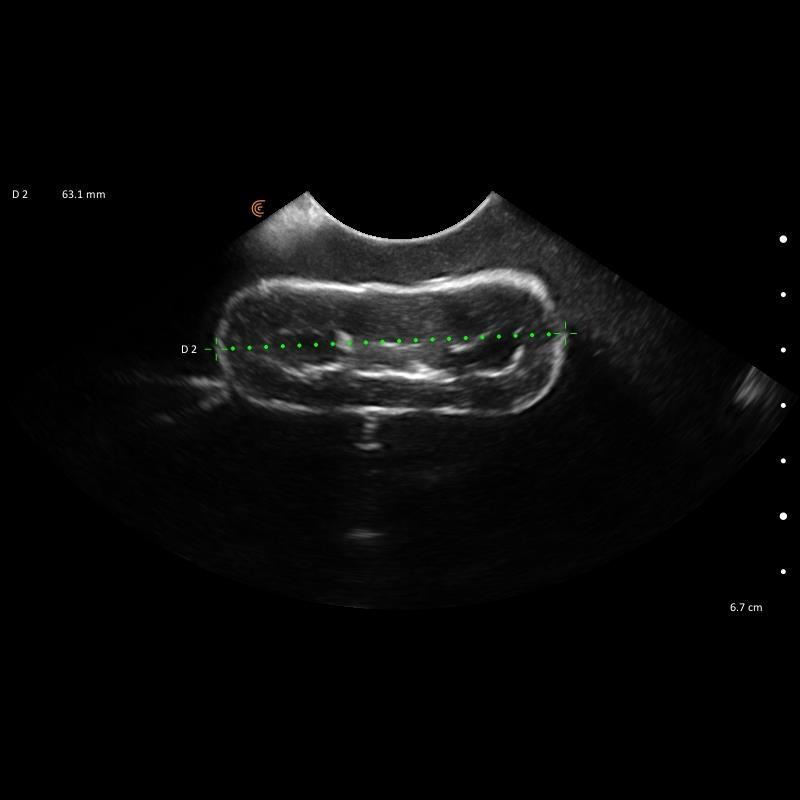

Le kit de formation fantôme à l’échographie canine "Lillie" Erler Zimmer est un outil indispensable pour la formation et la pratique en échographie vétérinaire. Conçu pour reproduire fidèlement l’anatomie canine, il permet aux professionnels de Santé vétérinaires, étudiants et praticiens expérimentés de s’entraîner de manière réaliste sur tous les organes majeurs : cœur, poumons, foie, pancréas, reins, intestins et système vasculaire.

Ce kit complet inclut le module “Skills”, qui enrichit l’apprentissage en proposant des structures anéchogènes, nodules hyperéchogènes et zones d’évaluation, idéales pour simuler des situations cliniques complexes. Le bloc FNA auto-réparant offre la possibilité de pratiquer des ponctions et gestes interventionnels en toute sécurité, garantissant un entraînement répétitif sans patient vivant.

Simulation complète des organes canins : cœur, poumons, foie, pancréas, reins, intestins, vessie et vaisseaux majeurs.

Module “Skills” avancé : nodules, structures anéchogènes et échogènes, vaisseaux spiraux pour un entraînement ciblé.